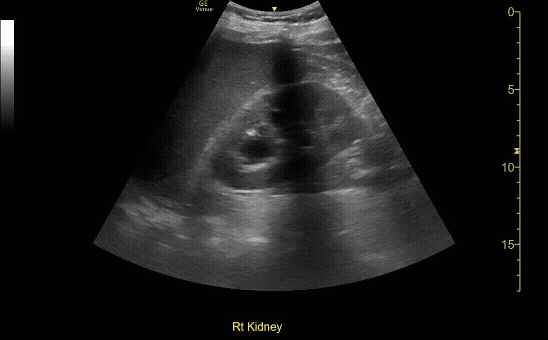

R/L kidney In transverse (short) view

c/o Victoria Gonzalez, MD